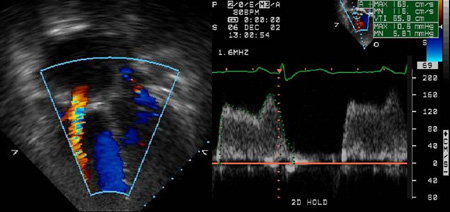

Tricuspid stenosis

Echocardiogram with colour Doppler reveals flow acceleration across the tricuspid valve and spectral Doppler reveals a mean TV gradient of 6 mmHg

From the personal collection of Martin Bocks; used with permission